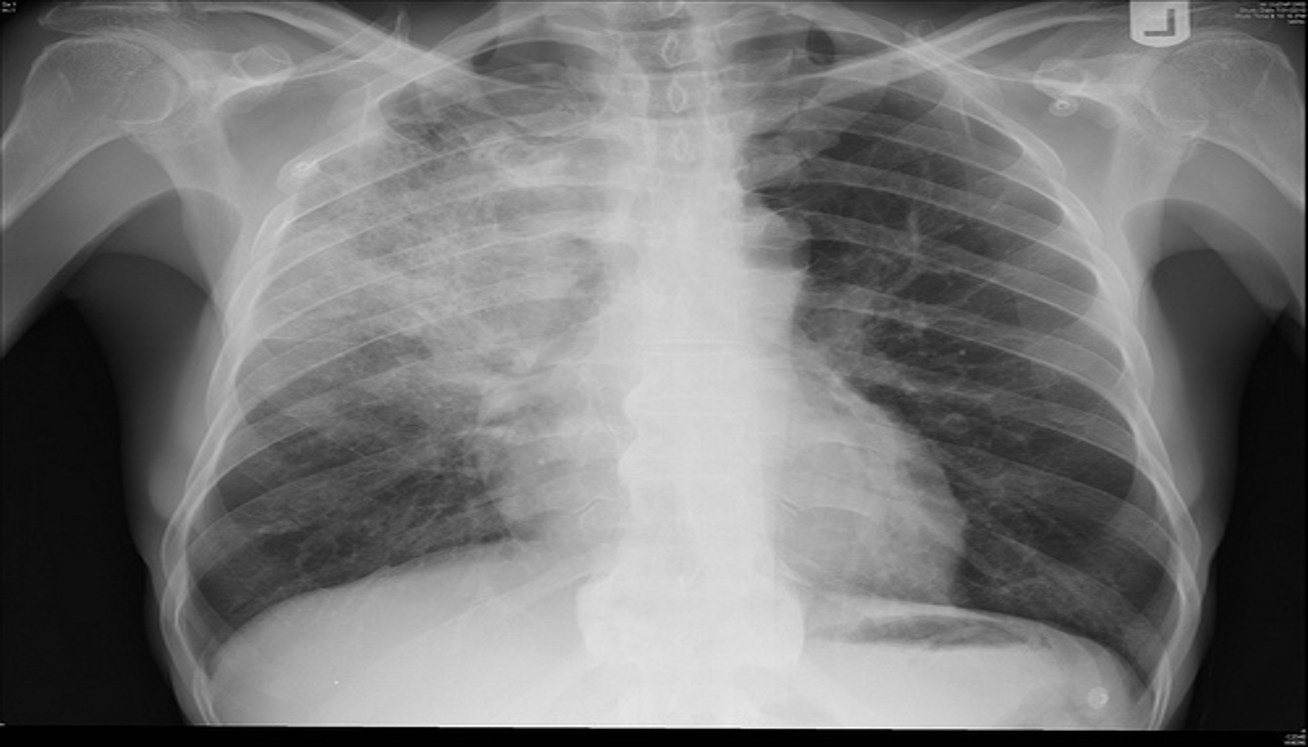

- CXR:

- The appearance of consolidation on CXR is reliable for the diagnosis of pneumonia, but CXR appearances are not reliable for distinguishing between viral and bacterial infection as there is considerable overlap.

- The CXR may appear normal early in the disease. However, as an approximate guide:

- Viral pneumonia:

- Patchy perihilar infiltration, hyperinflation, atelectasis

- Bacterial pneumonia:

- Lobar consolidation (air bronchogram) occasionally with parapneumonic effusion. Pneumatocoele and abscesses suggest staphylococcal pneumonia

Chest X-Ray showing patch of pneumonia

Image of chest x-ray displaying the interstitial pattern seen in viral pneumonia. The interstitial pattern shows fine lines radiating from the hila.

These chest X rays compare clear, healthy lungs with the cloudy, inflamed lung tissue of pneumonia.

Right lower lobe consolidation in a patient with bacterial pneumonia.